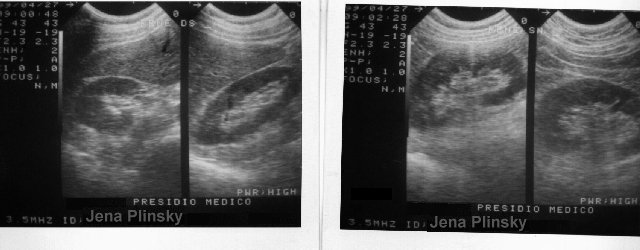

rene destro e sinistro...anche qui nulla di anomalo... alcuni gi� parlano di miracolo... |